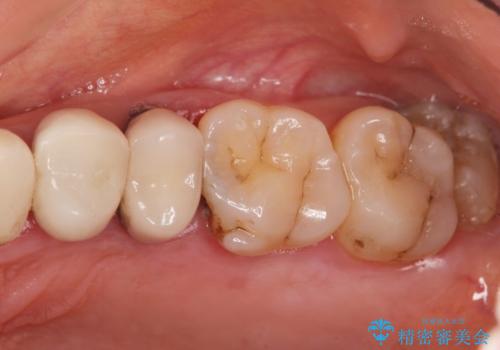

- 黒く変色し、ぐらぐらする歯の改善を求めて来院されました。

X線、歯周組織検査の結果、残すことができない歯周病の進行が左上小臼歯に認められました。

抜歯後は、インプラントではなくブリッジを選択されました。

最終的なブリッジの清掃性を高めるため、歯ぐきのボリュームがこれ以上減少しないよう抜歯時に歯槽堤保存術を行うような工夫をしています。